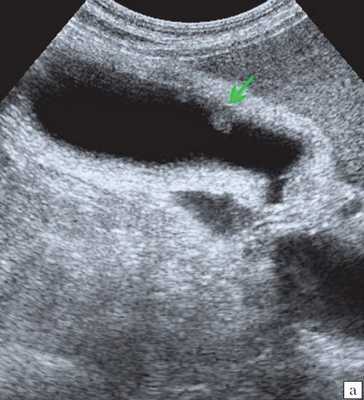

Ультрасонография является эффективным средством выявления полиповидной формы холестероза 6. Традиционной считается следующая сонографическая характеристика холестериновых полипов: неподвижные гиперэхогенные структуры, которые не дают акустической тени и прикрепляются к стенке желчного пузыря. Контуры таких образований, как правило, ровные, а размеры таких образований различны, чаще не превышают 10 мм (рис. 2).

a) Одиночный полип в желчном пузыре (гиперэхогенное пристеночное неподвижное образование, с ровными контурами, без акустической тени).

б) Одиночный полип в желчном пузыре.